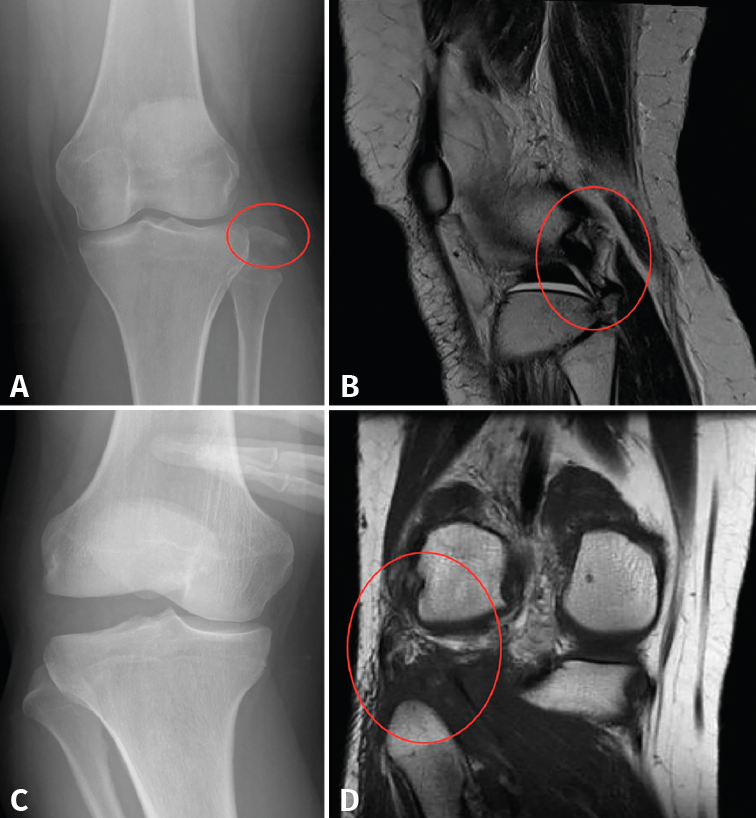

Figura 1. A: radiografía anteroposterior (AP) de rodilla, fractura-avulsión de la cabeza del peroné (círculo rojo) por lesión del complejo posterolateral (CPL); B: corte sagital de resonancia magnética del caso mostrado en la imagen A, en el que se evidencia la lesión del CPL (círculo rojo); C: radiografía AP en estrés de rodilla con bostezo al varo de grado III, por lesión del CPL; D: corte coronal de resonancia magnética del caso mostrado en la imagen C, donde se evidencia la lesión del CPL (círculo rojo).